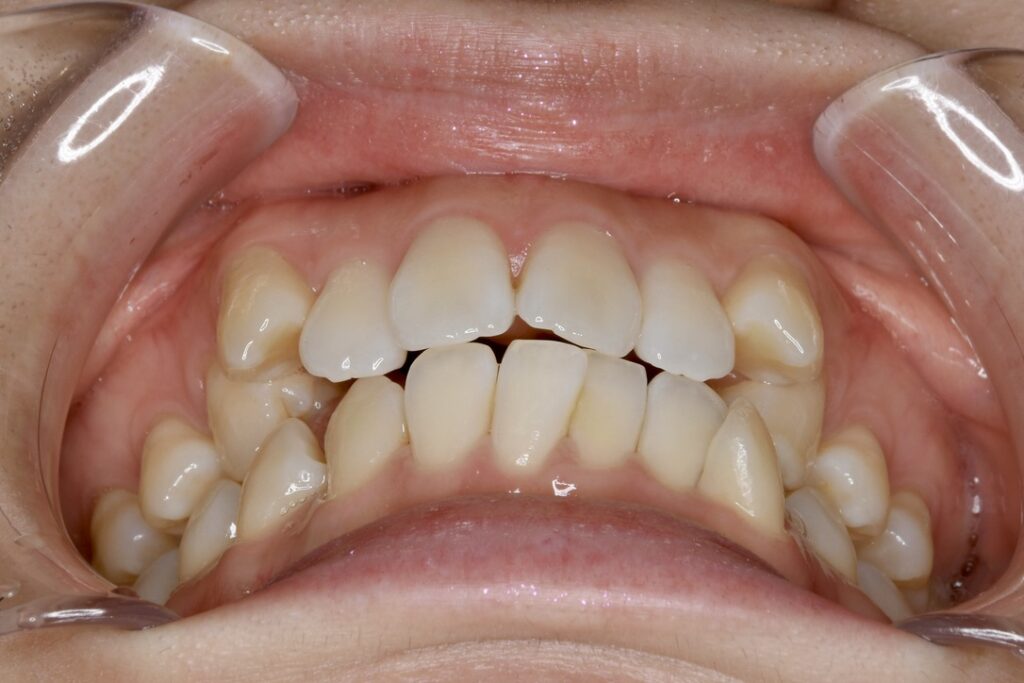

| 主訴 | 上も下も歯並びがガタガタしているので治したい。 |

|---|---|

| 診断名・主な症状 | 叢生 |

| 年齢 | 18歳 |

| 治療内容 | 上下とも歯並びの横幅を広げながら、でこぼこを解消しました。 |

| 使用装置 | マウスピース矯正装置(インビザライン) |

| 抜歯部位 | 抜歯なし |

| 治療期間 | 1年4ヶ月 |

| 通院回数 | 10回 |

| 費用 |

86万円程度(税別) 33990 |

| リスク・副作用 | 痛み、歯肉退縮、歯根吸収、抜歯に伴う出血や腫れが生じることがあります。 |